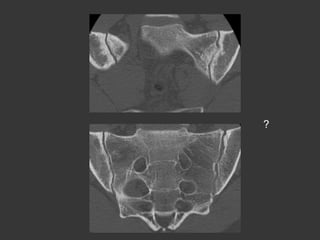

Mr B., 20 years old

Inflammatory Low back pain

?

Inflam. Rh.

HyperParaTh

SPA

Psoriasis

SAPHO

Sacro-iliac(s)?

(Entérocolopathy)

Osteoarthritis

Infectious

Teenager:

Pseudo-enlargment

Para articular bone